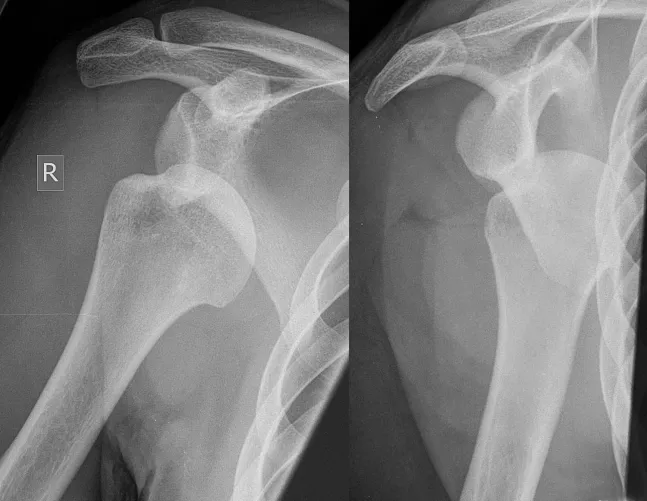

Bárkinél könnyen kialakulhat a leggyakoribb ficam, az emberi szervezet legszabadabban mozgatható ízületét érintő vállficam. Buszon, villamoson, fej felett kapaszkodva, hirtelen fékezéskor, illetve nyújtott karra eséskor a felkarcsont nagy ízületi fejecse kiugrik a lapocka sekély ízületi vápájából.

A sérüléses eredetű ficamoktól el kell különíteni az úgynevezett szokványos ficamot, amely leggyakrabban szintén a vállízületnél fordul elő. Szinte mindennapos sportolóknál, elsősorban tornászoknál, úszóknál. Erőteljes karmozdulatra vagy viszonylag kis erőbehatásra a felkar kiugrik a helyéről. Akinél gyakran előfordul, olykor képes saját magának is helyretenni a kificamodott felkart. Véglegesen csak műtéttel kezelhető.